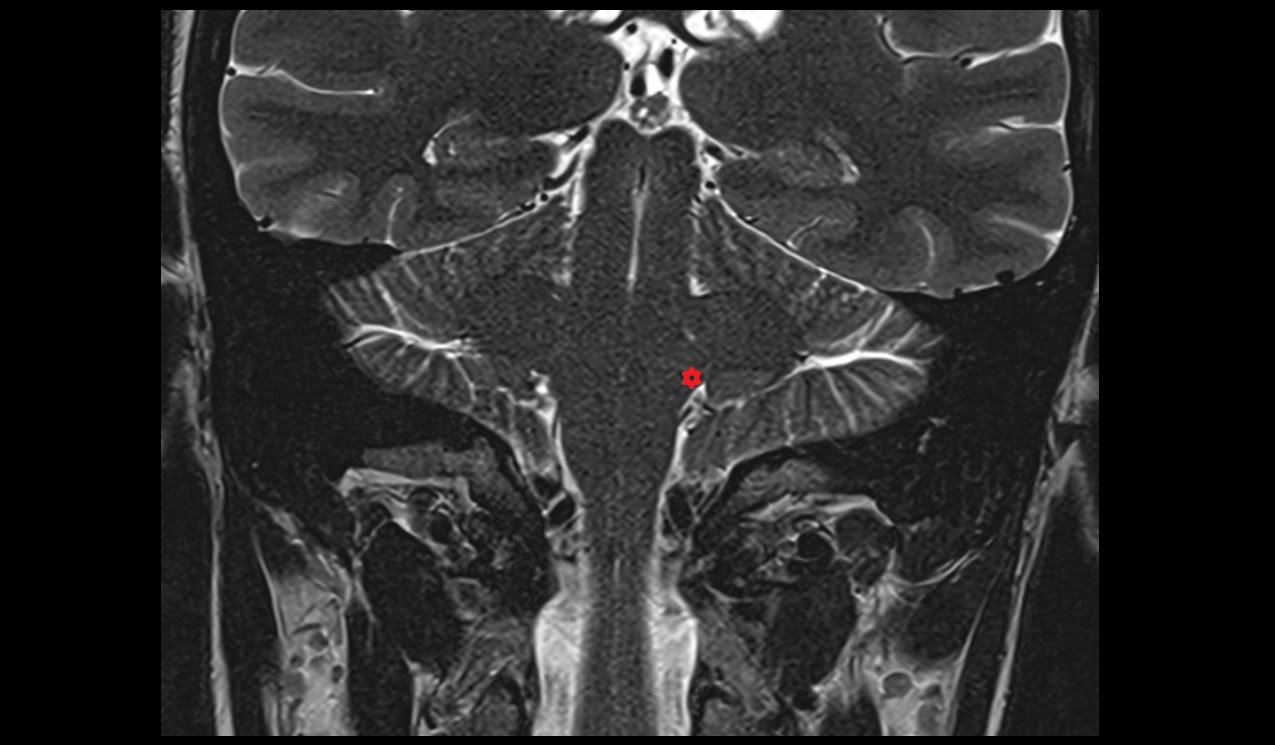

- Cerebellum

- Dentate nucleus

- Quadrigeminal cistern